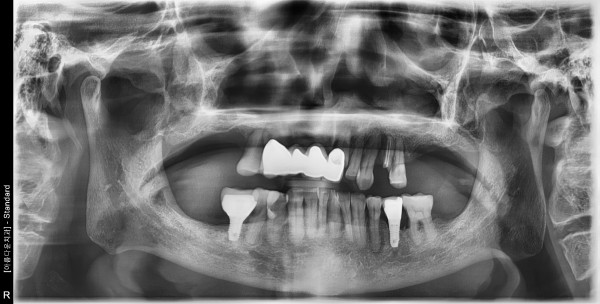

82세 남자환자 / 상악 풀케이스 ( 뼈이식 및 임플란트식립)